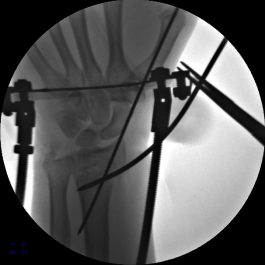

5.使用执行器夹持克氏针,于掌侧穿针,撬拨骨块并使用六轴机器人固定针末端以维持撬拨位置。

6.六轴机器人撬拨骨块过程